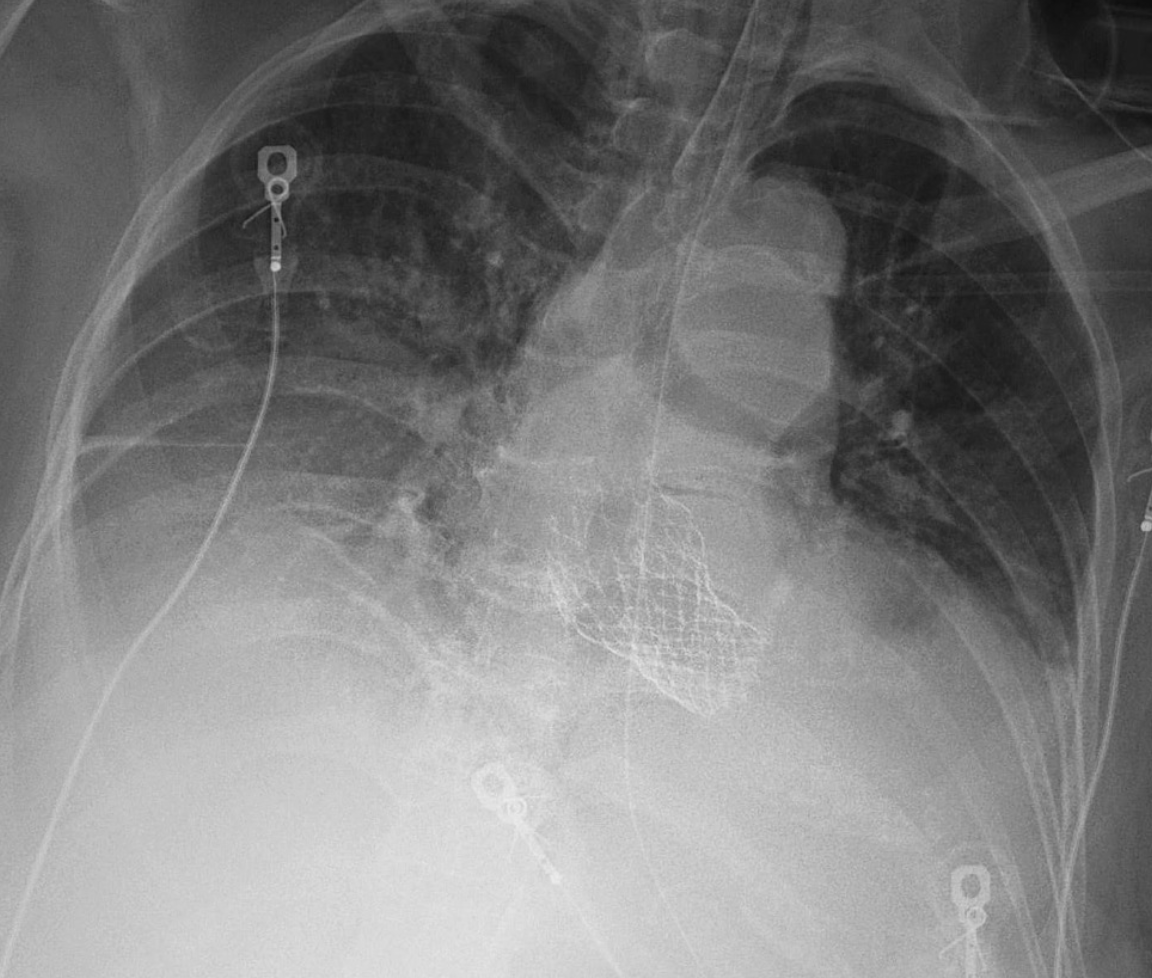

A

-TAVR

-Single lead RV pacemaker

-Telemetry leads